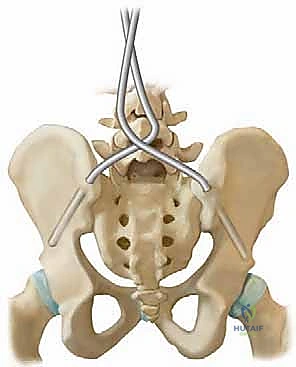

Distal fixation is arguably the most critical component of the construct, as failure to adequately control the pelvis will result in recurrent obliquity and sitting imbalance. The Galveston technique, or modern variations utilizing intra-iliac posts or screws, relies on the robust cortical bone between the inner and outer tables of the ilium. The optimal trajectory begins at the posterior superior iliac spine (PSIS) and advances anteriorly and distally, passing just superior to the greater sciatic notch. This trajectory maximizes bone purchase while avoiding the sciatic nerve and the superior gluteal neurovascular bundle. The surgeon must possess a pristine three-dimensional understanding of the pelvic anatomy, as the ilium in neuromuscular patients is often dysplastic, narrow, and severely rotated.

Biomechanically, the unit rod construct is a masterpiece of load-sharing and stress distribution. By utilizing a single, continuous, pre-contoured rigid rod (typically 1/4 inch or 3/16 inch stainless steel) and securing it at every available segmental level with sublaminar wires, the construct dissipates corrective forces across the entire length of the spine. This minimizes the stress concentrated at any single bone-implant interface, drastically reducing the risk of implant pullout in osteopenic bone. The primary corrective maneuver is a powerful cantilever force. The distal limbs of the unit rod are first docked into the ilium. The proximal U-shaped portion, which initially stands proud of the kyphoscoliotic thoracic spine, is then gradually leveraged down to the midline. This maneuver translates the spine to the rod, simultaneously correcting the coronal deformity, restoring sagittal contours, and forcefully leveling the pelvis.

2. Preparation of the Pelvic Foundation (Galveston Technique)

The foundation of the unit rod construct lies in the pelvis. The PSIS is identified, and a starting hole is created using a burr or awl. The trajectory is critical: the drill must pass between the inner and outer tables of the ilium, directed roughly 15 degrees laterally and 15 degrees caudally, aiming just superior to the sciatic notch.

A blunt probe is utilized to palpate the trajectory, ensuring there is no cortical breach into the sciatic notch or the true pelvis. Once the trajectory is confirmed, the pathway is sequentially enlarged to accommodate the distal limbs of the unit rod.

The correct width of the U-rod is selected to sit comfortably across the laminae. The rod is then introduced to the sterile field. The distal limbs are simultaneously impacted into the bilateral iliac holes. At this stage, the proximal U-portion of the rod will be standing high above the thoracic spine due to the uncorrected deformity.